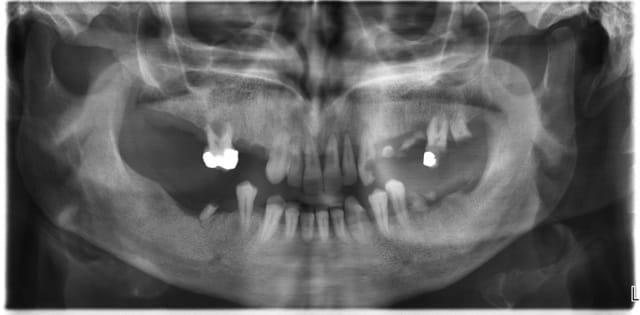

3ème photo: radio d´un patient âgé de 73 ans qui souhaitait avoir des dents fixées.Comme on l´observe il n a plus de place après les foramines mentales.Nous avons donc utilisé juste l´os interforaminal. Nous avons suivi le concept du prof. Nentwig qui consiste à pouvoir ajouter 2 dents dans chaque quadrant dans la mandibule.

Mon guide était l´ancienne prothèse avec laquelle j´ai fait un OPG en plaçant un trombone metallique entre les dents 4 et 5 dans la prothèse, ainsi j ai pu utiliser la prothèse comme un guide pour éviter un problème avec la zone foraminale....